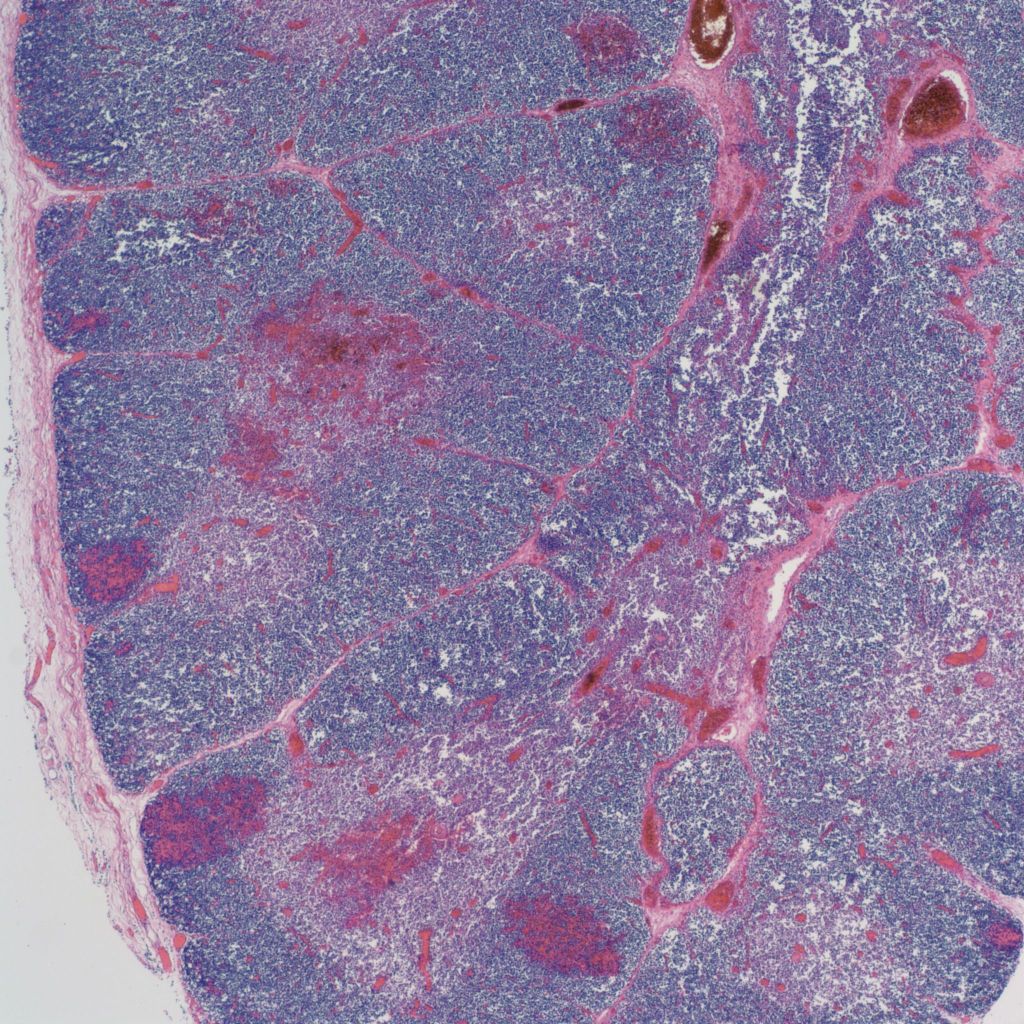

The thymus normally involutes as the infant ages. However, in some stillborn infants, usually with a chronic stress such as infection, fetal hydrops or growth restriction, there is accelerated involution, that is loss of the lymphocytes in the cortex of the thymus. An early phase of this process is often seen in response to chorioamnionitis. In the acute cases, the prominent abnormality is a “starry sky” appearance due to the lymphorrhagia (phagocytosis) of cortical lymphocytes. Low magnification microscopy demonstrates open spaces in the cortex reminding some observers of a “starry sky”. (Fig 9,10) At higher magnification, these apparent spaces can be seen to be the cytoplasm of a large cell often with small, fading nuclei of small lymphocytes within.

As involution progresses, there will be a progressive loss of cortical lymphocytes. The cortex will appear notably thinned compared to the medulla with thinner lobules and more connective tissue between lobules (Figs 11a, 11b, 12a, 12b, 13a, 13b).

At the extreme, the medulla will appear to have the only small lymphocytes in the thymus, giving an inside out appearance at low magnification (fig 14, 15).